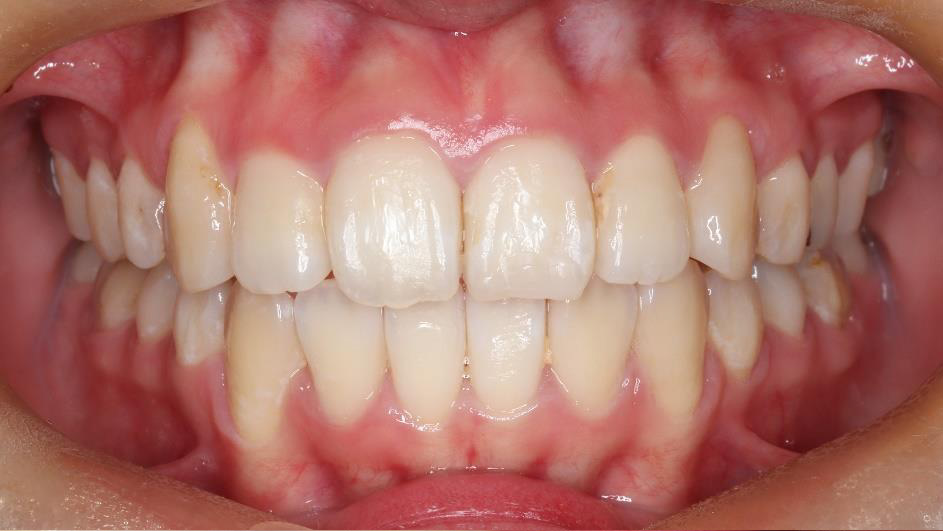

治療前

治療終了前

でこぼこがある状態になります。乱ぐい歯とも言われます。見た目がよくない審美障害が主な問題点ですが、その他にもでこぼこが多いことで、歯ブラシによる清掃性が悪くなり、結果、虫歯や歯周病のリスクも上がってしまいます。治療期間が短く済むことも多い為、気になった段階で早期に相談された方が良いと思います。